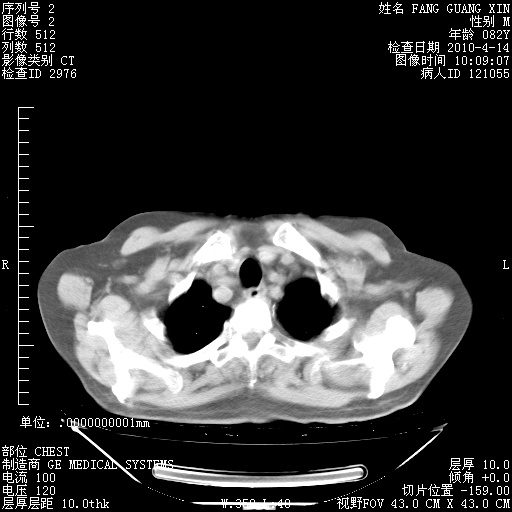

4月14日肺部CT

23.JPG

24.JPG

25.JPG

26.JPG